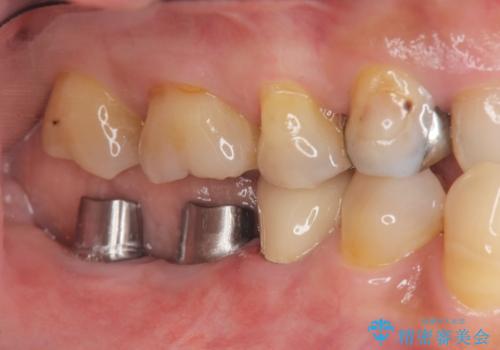

- 「奥歯で噛むと痛い、いつも膿のにおいがして不快、改善してほしい。」と治療を希望され来院されました。

精査した結果、奥歯の根は破折しており抜歯を避けられない状況でした。

咬合力が強く、その他の歯の破折も防ぐために奥歯の咬合機能をインプラントを用いて回復する治療計画を立てます。

- 99万円(インプラント×2・チタンカスタムアバットメント×2・ジルコニアクラウン×2・仮歯×2)費用は治療当時の料金となります